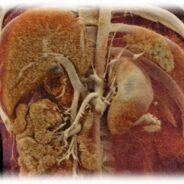

Pár kép az oktatás radiológiai részéről:

(SE-OKK, SIEMENS, CTISUS)